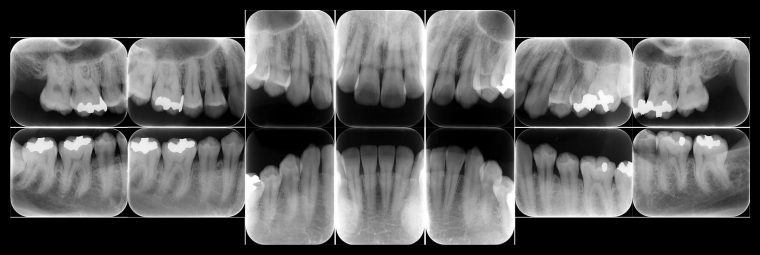

レントゲン写真

症例

レントゲンで骨のレベルがしっかりとあることが確認できました。